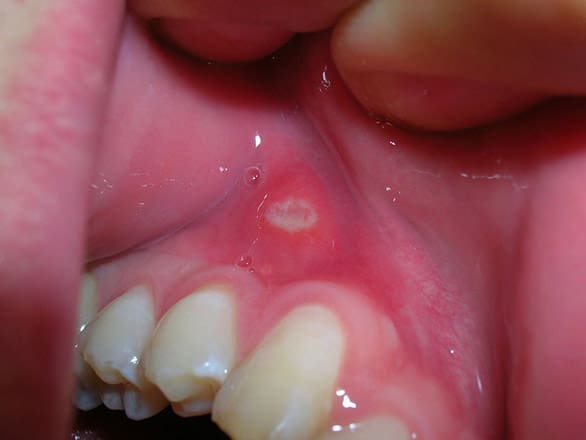

Canker sores: These painful, round or oval lesions can develop on the mouth or gums, making eating and speaking uncomfortable. Relief can be found through oral steroids, ointments, and salt water rinses.